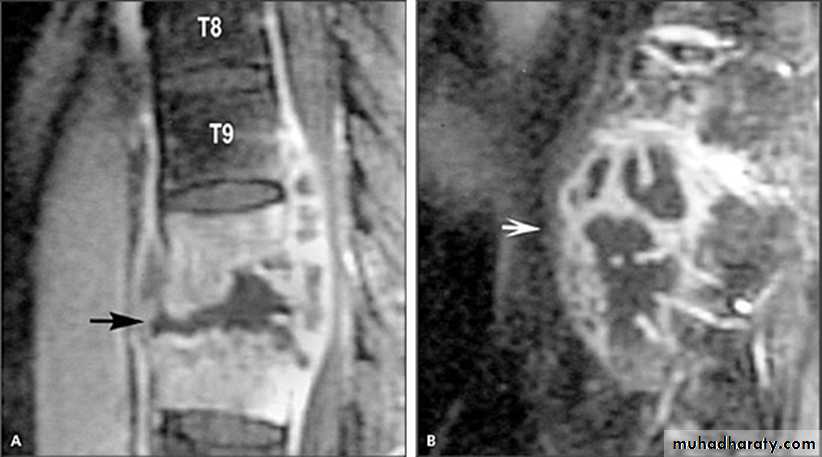

Haemangioma of the vertebral body of L3.

The whole body is marked by the characteristic vertical striationThe body of thoracic v. appeared as an area of high signal intensity on T1-T2-weighted images (a and b)